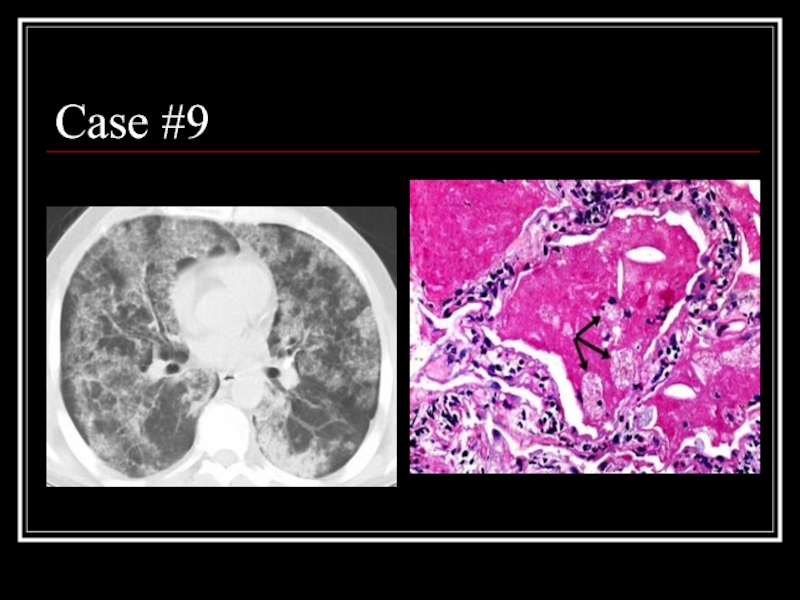

Слайд 35Case #9

Слайд 36Answer: PAP

CT: patchy ground glass opacities and septal thickening in a

geographic distribution

Path: intra-alveolar accumulation of surfactant components and cellular debris, with minimal interstitial inflammation or fibrosis